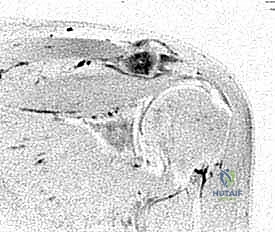

2. التصوير الطبي المتقدم (Medical Imaging)

- الأشعة السينية (X-rays): يتم أخذ صور بوضعيات خاصة (مثل Zanca view) لتقييم المفصل بدقة، حيث تظهر تضيق المسافة المفصلية، التصلب العظمي (Sclerosis)، والنتوءات العظمية، أو التكيسات العظمية (في حالات رافعي الأثقال).

- التصوير بالرنين المغناطيسي (MRI): يُعد أداة حاسمة ليس فقط لتقييم درجة تلف الغضروف والتهاب نقي العظم في الترقوة، ولكن الأهم من ذلك، لاستبعاد أي تمزقات مرافقة في أوتار الكفة المدورة، والتي تتواجد بشكل متزامن في نسبة كبيرة من المرضى.